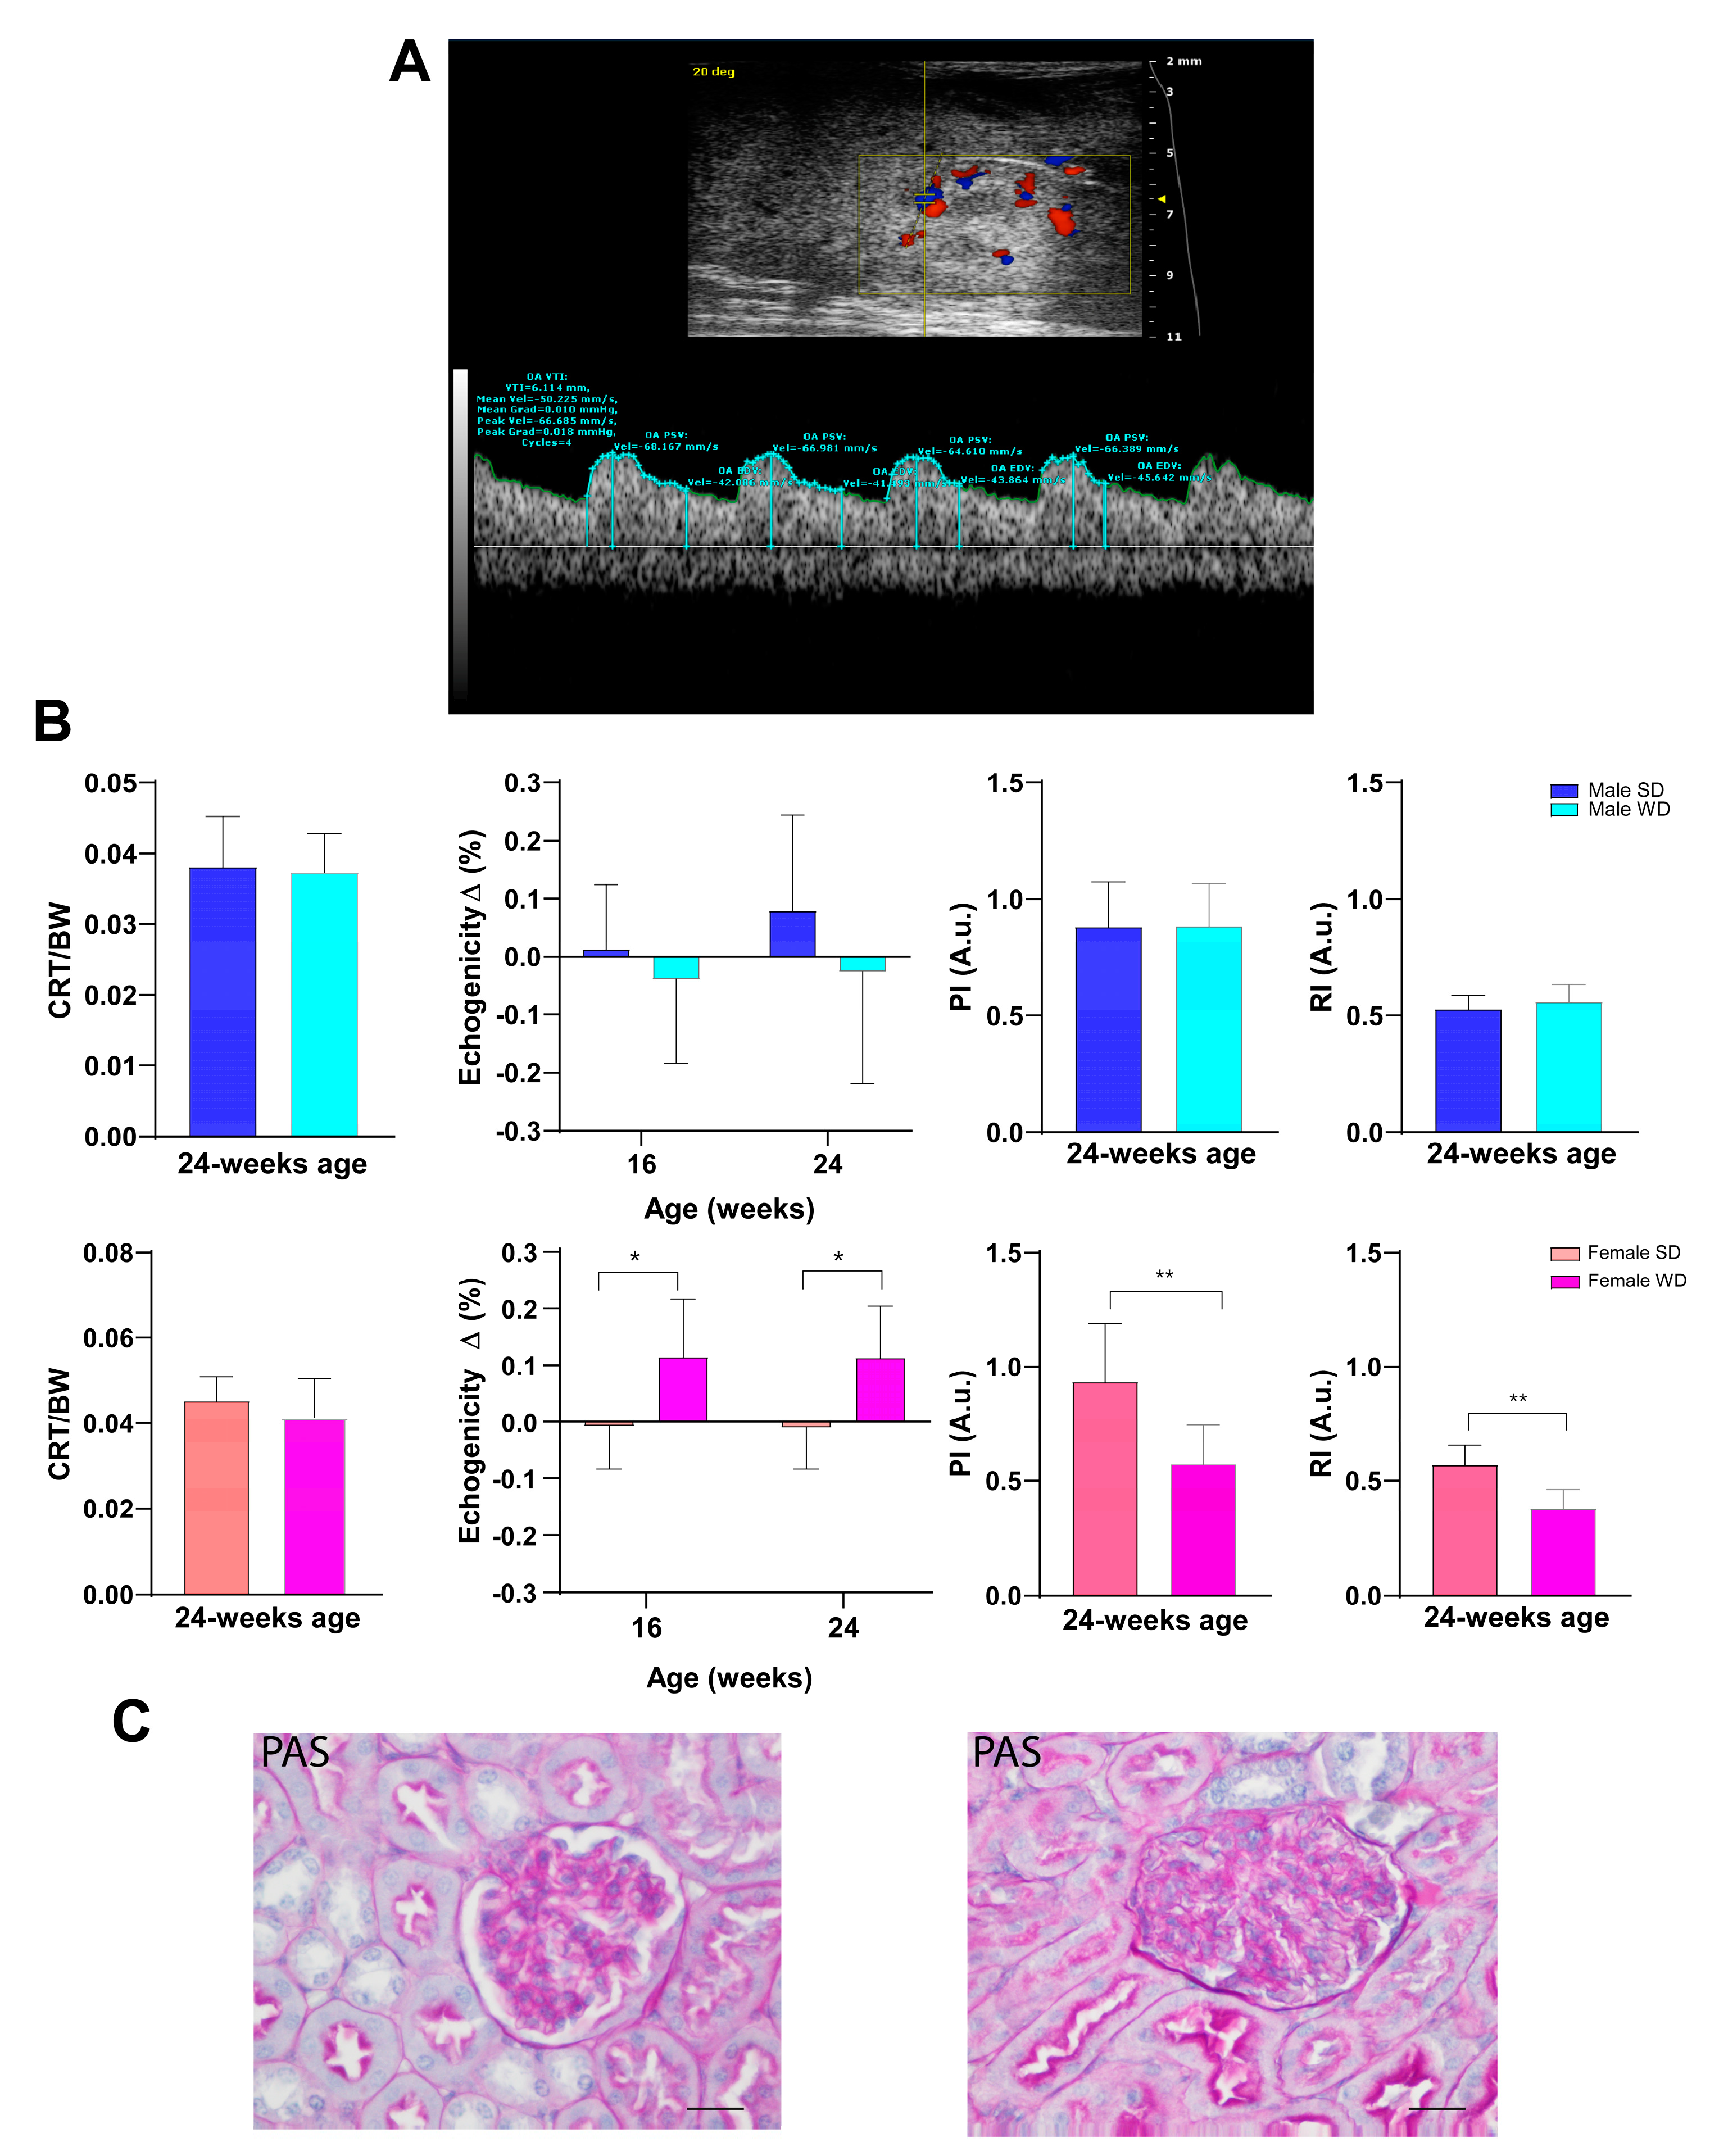

3.6. WD Causes Progressive Structural and Functional Changes in the Heart, Liver, and Kidney of C57Bl/6J Mice That Can Be Detected Early and Monitored In Vivo by HFUS